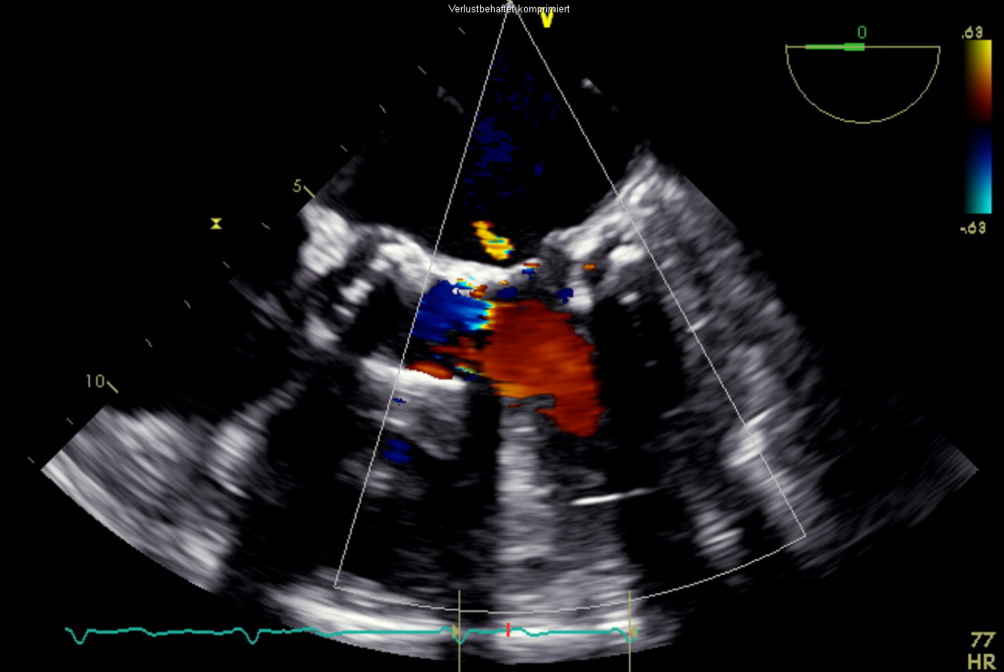

In der transösophagealen Echokardiographie zeigte sich eine deutlich exzentrische, hochgradige Mitralklappeninsuffizienz aufgrund eines partiellen Sehnenfadenabrisses im Segment P2 mit einem nach posterior gerichteten Jet (Abb. 1 und 2). Des Weiteren zeigten sich eine gute systolische linksventrikuläre Funktion und kein Hinweis auf einen Shunt auf Vorhofebene. Eine echokardiographische Abklärung des rechten Ventrikels ergab eine visuell leicht reduzierte Funktion bei einer reduzierten Anulusgeschwindigkeit von 7 cm/s, jedoch noch erhaltener longitudinaler rechtsventrikulärer Funktion („tricuspid annular plane systolic excursion“ 2 cm). Des Weiteren wurde eine mittelgradige Trikuspidalklappeninsuffizienz bei Anulusdilatation festgestellt.

Abb. 2

Transösophageale Echokardiographie. 2‑D-Ansicht im 3‑Kammer-Blick auf die Mitralklappeninsuffizienz mit nach posterior gerichtetem Jet

Bild vergrößern